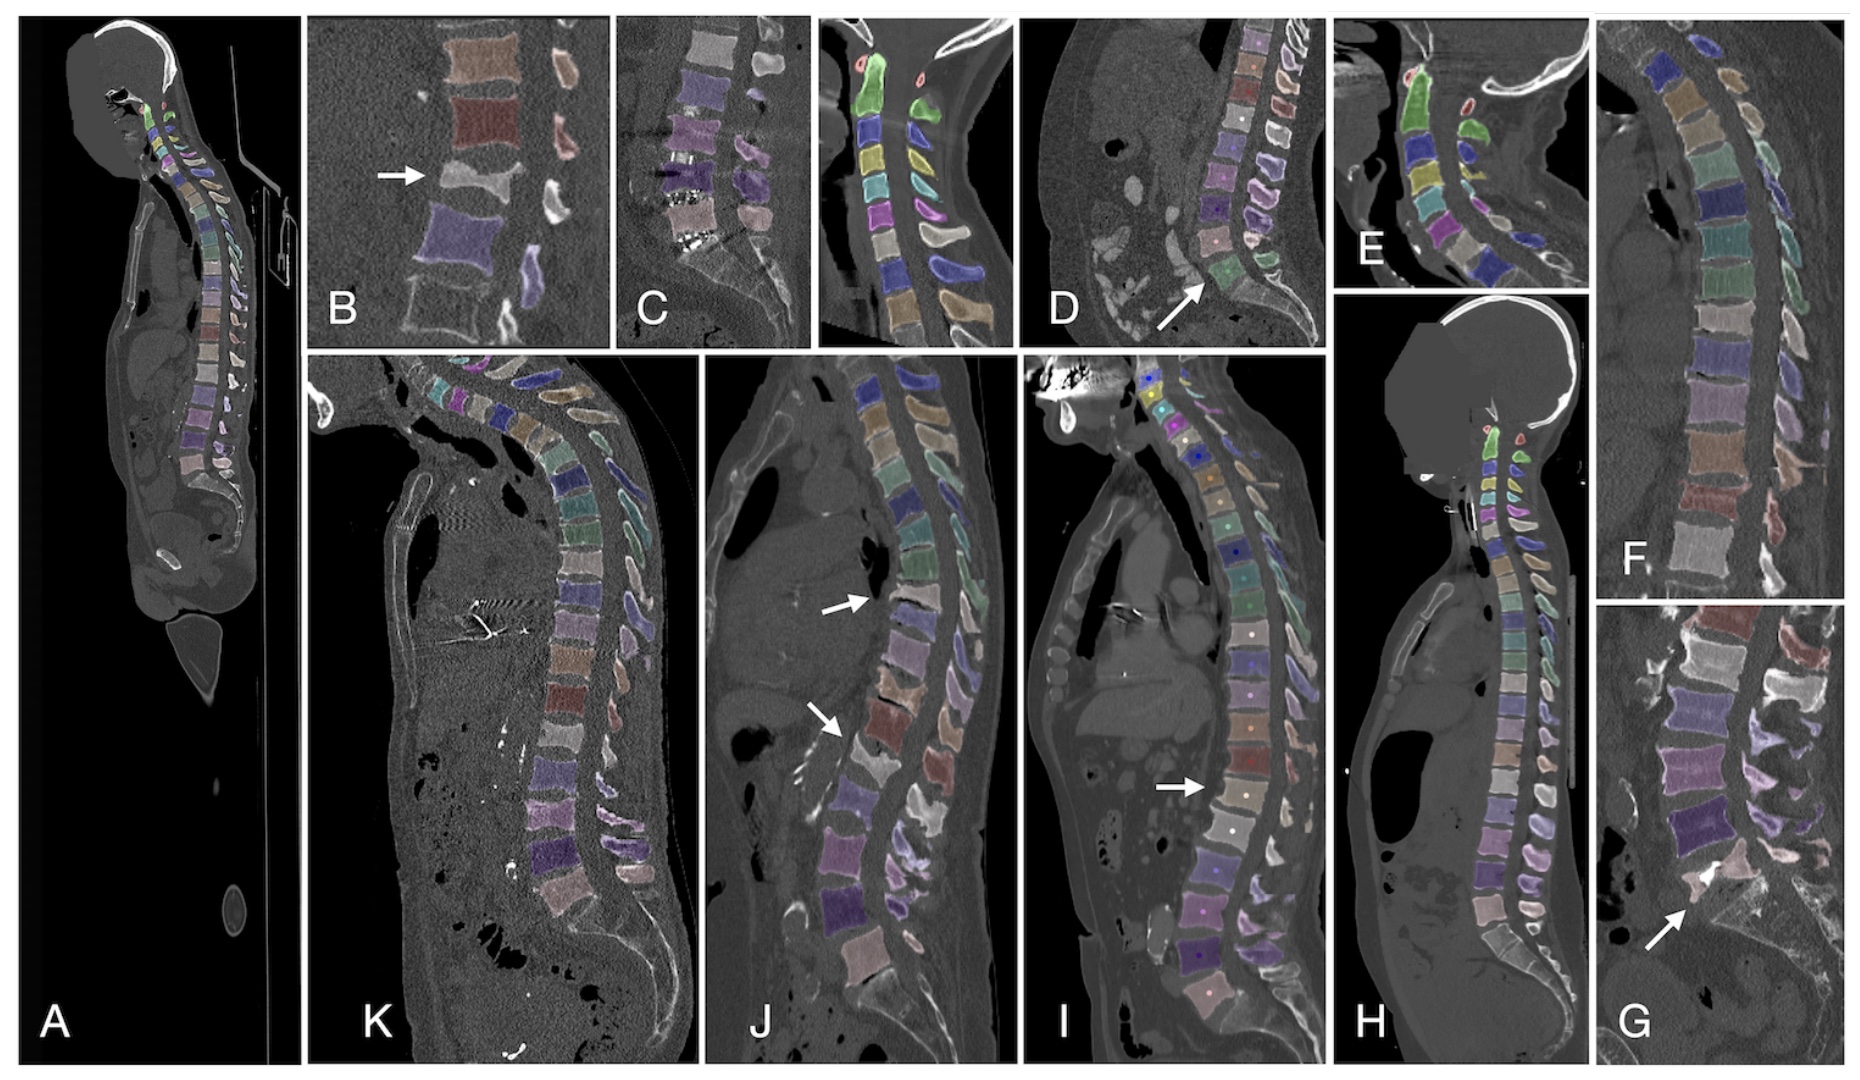

VerSe stands for Large Scale Vertebrae Segmentation Challenge, which is a large-scale, multi-detector, multi-site spine CT dataset. The dataset includes 374 scans from 355 patients. This challenge was held in conjunction with MICCAI 2019 and MICCAI 2020. The evaluation tasks include: vertebrae annotation and segmentation.